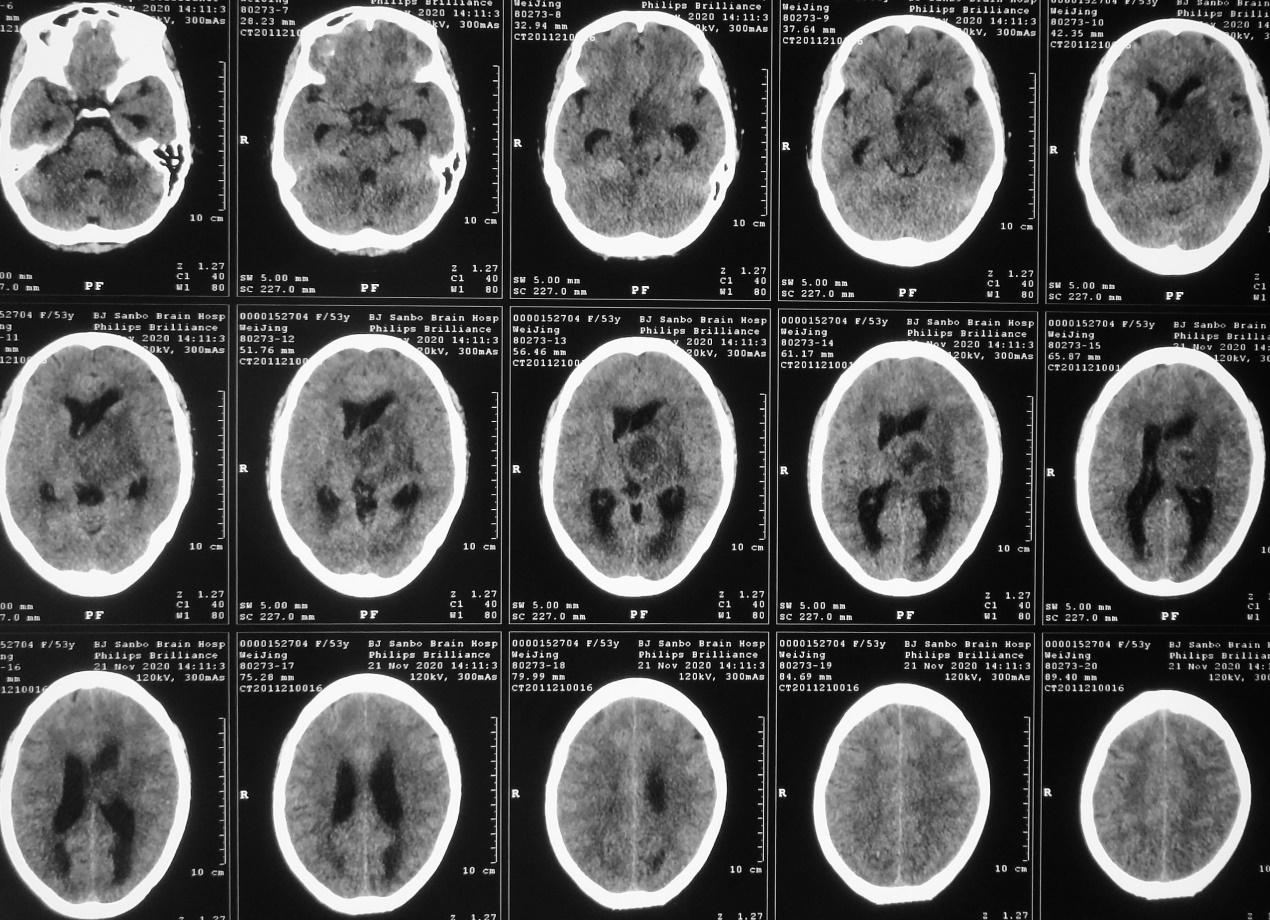

入院当天,患者出现恶心、呕吐数次,意识变差呈昏睡状态,强刺激才能睁眼。复查头颅CT见左侧丘脑病变增大,周围水肿明显,脑室扩张( 图-3 ),医生给予脑室穿刺外引流术。

图-3: 2020年11月21日头CT

脑室外引流术后第2天即2020年11月22日早上8点,患者好转为清醒,复查头颅CT见左侧脑室缩小( 图-4 );但患者出现发热,引流出的脑脊液浑浊,医生考虑患者丘脑病变为脑脓肿,给予头孢曲松抗炎治疗。

图-4: 2020年11月22日头CT